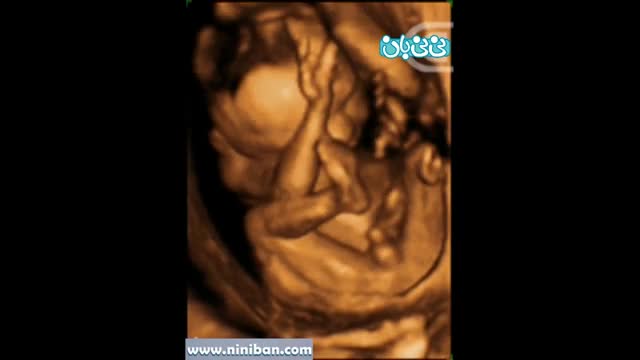

سونوگرافی چهار بعدی در بارداری هفته شانزدهم

۰۰:۲۰